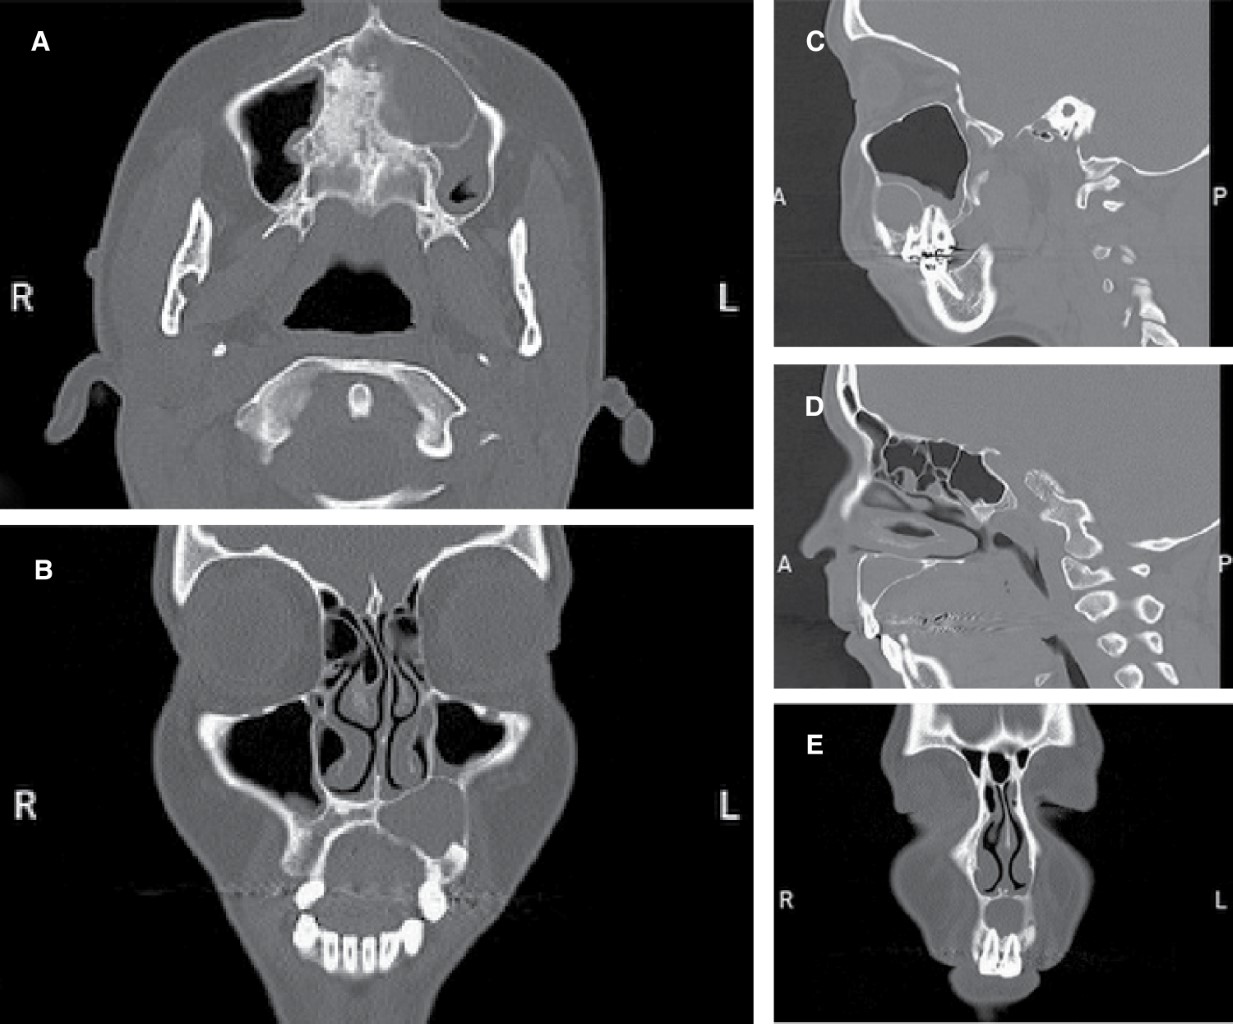

• 4) Removal of the lesion remnant and placement of bone substitute on a delayed basis: after eight months of decompressive treatment, the patient requested a surgical lesion cleaning, so the cystic remnant was removed using general anesthesia. A mucosal flap extending from the right lateral incisor to the left second molar was done. After separating of the mucoperiosteum, the cystic bed was curetted; detachment of its capsule and placement of injectable synthetic bone substitute paste, composed of 55% dehydrated dicalcium phosphate, 45% tricalcium phosphate with bioconductive power to fill the collapsed bone after residual cystectomy, were performed (Figure 5 A and B). Next, the bone substitute was covered with a resorbable collagen membrane. Later, the drainage placed in the first diagnostic surgery was removed. Finally, the mucoperiosteal flap repositioned and sutured at separate points. The histopathological diagnosis of the enucleated lesion confirmed the initial diagnosis (inflammatory maxillary cyst).

• Figure 5C was obtained immediately after the placement of the bone substitute. A clinical and radiographic follow-up was carried out throughout its evolution with highly satisfactory results (Figure 5D shows the status of the problematic tooth and standard peri-dental tissues related to the bone substitute). To date, the patient has been under control for two years, observing the absence of recurrences and preserved pulp vitality of the previously involved pieces.